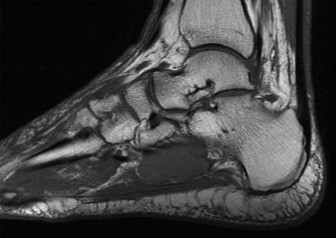

Figure 1: Representative Sagittal T2-weighted MRI image demonstrating a severely displaced talar neck fracture (Hawkins type III/IV). Note the significant angulation and posterior displacement of the talar body relative to the ankle mortise, and extensive bone marrow edema. The fracture line extends into the posterior subtalar joint. Soft tissue swelling and potential ligamentous injury are also evident.

Crucial MRI Sagittal Insights:

The MRI sagittal images proved indispensable for a complete understanding of the injury pattern, exceeding the capabilities of CT for soft tissue and cartilage assessment.- Ligamentous Integrity: Sagittal views provided excellent visualization of the calcaneofibular ligament, posterior talofibular ligament, and particularly the deltoid ligament complex. In this case, significant edema and partial tearing of the deep deltoid ligament were noted, correlating with the medial clear space widening on X-ray. Sagittal images are also superior for assessing the interosseous talocalcaneal ligament, a critical stabilizer of the subtalar joint, which showed signs of disruption.

- Articular Cartilage Assessment: While CT shows bone, MRI sagittal views exquisitely demonstrate the integrity of the articular cartilage. We observed areas of chondral bruising and early subchondral edema on the talar dome, consistent with impaction. Furthermore, articular step-offs and incongruity in both the tibiotalar and subtalar joints were precisely quantified, guiding the need for meticulous anatomical reduction.

- Talar Head and Neck Morphology: The sagittal images provided a detailed profile of the fracture lines through the talar neck and body, allowing for precise measurement of anterior, posterior, and superior displacement and angulation. This was critical for understanding the extent of shortening and the specific vector required for reduction. They also helped identify small, non-displaced fracture lines or occult fractures that might be missed on CT, particularly in areas of complex anatomy.

- Subtalar Joint Involvement: The sagittal plane is paramount for evaluating the posterior facet of the subtalar joint. In our patient, the fracture clearly extended into this joint, with significant displacement of the posterior talar facet, highlighting the necessity for accurate reduction of this weight-bearing surface to prevent post-traumatic arthrosis.

- Associated Soft Tissue Injuries: Beyond ligaments, MRI sagittal views allowed assessment of surrounding tendons (e.g., flexor hallucis longus, posterior tibialis, Achilles tendon), demonstrating tenosynovitis or contusion which could impact post-operative recovery. Assessment of the posterior neurovascular bundle can also be achieved.

- Vascularity Assessment (Indirect): While direct visualization of vessels requires angiography, MRI provides indirect signs related to vascular compromise. The extent of fracture displacement and soft tissue injury can correlate with the risk of AVN. Advanced sequences, though not routine for initial trauma, can sometimes show perfusion changes.